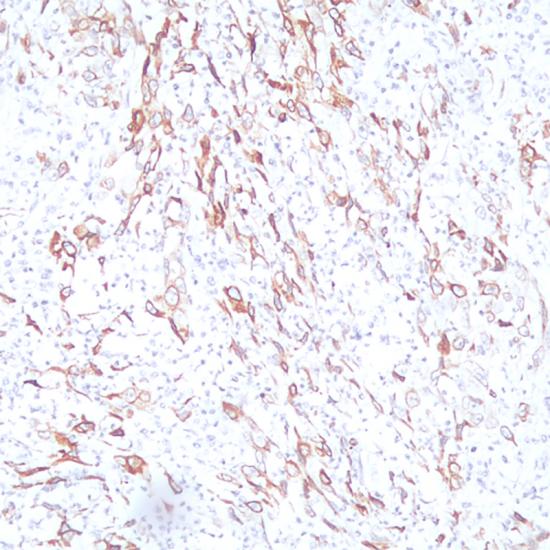

COX-2抗體試劑(免疫組織化學(xué))    閩廈械備20180198號

• 預(yù)處理:

熱修復(fù)

• 陽性部位:

細(xì)胞漿/細(xì)胞膜

• 陽性對照:

肺鱗癌

環(huán)氧化物酶可以通過催化精氨琥珀酸合成環(huán)內(nèi)過氧化物而形成前列腺素,具有兩種異構(gòu)體形式:COX-1和COX-2,COX-2是—種誘導(dǎo)型酶。COX-2被認(rèn)為是免疫調(diào)節(jié)研究中的一個(gè)理想標(biāo)記物和 抗炎性疾病的治療靶標(biāo)。COX-2的表達(dá)或過表達(dá)與癌生成有關(guān)。在直腸癌、肺癌、食道癌、前列腺癌、乳腺癌和卵巢癌中均有表達(dá)。